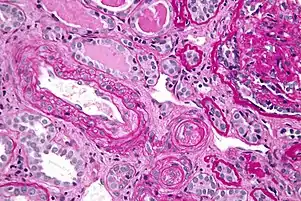

In the kidneys, chronic hypertension has a great impact on the kidney vasculature, leading to pathologic changes in the small arteries of the kidney. Affected arteries develop endothelial dysfunction and impairment of normal vasodilation, which alter kidney autoregulation. When the kidneys' autoregulatory system is disrupted, the intraglomerular pressure starts to vary directly with the systemic arterial pressure, thus offering no protection to the kidney during blood pressure fluctuations. The renin-aldosterone-angiotensin system can be activated, leading to further vasoconstriction and damage. During a hypertensive crisis, this can lead to acute kidney ischemia, with hypoperfusion, involvement of other organs, and subsequent dysfunction. After an acute event, this endothelial dysfunction has persisted for years.[3]